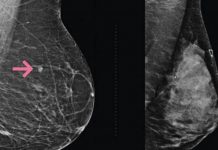

Nieuwe Israelische methode ontdekt in vroeg stadium borstkanker

Onderzoekers van de Ben-Gurion Universiteit in samenwerking met het Soroka Universitair Medisch Centrum in Beër Sjeva hebben de ontwikkeling aangekondigd van een nieuwe en nauwkeurige methode voor screening op borstkanker in een vroeg stadium.